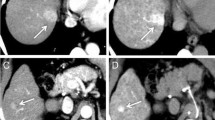

A 49-year-old woman with well-differentiated HCC. a Computed tomography during arterial portography shows small round perfusion defect in segment VIII (arrows). b Computed tomography during hepatic arteriography shows well-defined homogeneous enhancement in segment VIII (arrows). c Gd-DTPA-enhanced hepatic arterial phase MR image shows homogeneous enhancement with a well-defined margin (arrows). d SPIO-enhanced T2*-weighted fast image with steady precession MR image (TR/TE: 150 ms/13 ms) shows area of low signal intensity (arrows) corresponding to lesion seen in a–c. Numerous low signal intensity nodules are regenerative nodules. Large nodule (arrows) that was proved to be hepatocellular carcinoma is same signal intensity as cirrhotic regenerative nodules. e Photograph of the surgical specimen shows tumor tissue with a trabecular pattern (hematoxylin and eosin, ×40)

SPIO-particles exhibit a tissue-specific biodistribution to the reticuloendothelial system. After IV injection, the SPIO-particles are cleared by macrophages and can be identified histologically in Kupffer’s cells of the liver. Dedifferentiated hepatic malignancies lack Kupffer’s cells; therefore, the T2 relaxation time of the tumors does not change after the administration of SPIO. The resulting loss of signal intensity from the liver, with tumor signal intensity unchanged, increases the lesion-to-liver contrast. Yamamoto et al. [11] reported the improved detectability of small HCC lesions after enhancement with ferumoxides; however, there are some possible limitations in using SPIO-enhanced MR imaging for the detection of HCC in patients with liver cirrhosis [13, 14, 17, 18, 19]. Hundt et al. [16] reported that cirrhotic liver tissue shows less response to SPIO particles than does healthy liver tissue, and the effect of SPIO on the liver in patients with severe liver cirrhosis was less response than in patients with mild liver cirrhosis. After IV administration of SPIO, the reticular fibrosis of severely cirrhotic livers showed high signal intensity, which can obscure small hepatic lesions, and some well-differentiated HCCs showed hypointense or isointense enhancement, relative to the surrounding liver parenchyma, indicating greater or similar uptake of SPIO in the tumor when compared with nontumorous areas (Fig. 2) [14, 17]. Moreover, the high signal intensity of vascular structures relative to the signal intensity of the liver parenchyma was the most frequent cause of false-positive results [18, 19]. In the present study, the sensitivities and specificities of SPIO-enhanced MR imaging were 74 and 88%, respectively. Furthermore, we found less diagnostic accuracy in SPIO-enhanced MR images than on combined Gd-DTPA-enhanced dynamic MR images and SPIO-enhanced MR images, and combined CTAP and CTHA (Table 1). The results of our study show the limitation used to SPIO-enhanced MR images as single-contrast-enhanced MR study for the detection of HCC in cirrhotic patients.